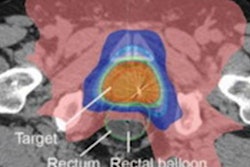

Although artificial intelligence (AI) algorithms have produced strong results in a wide range of clinical applications, most analyses have taken place in a simulated or lab environment. To assess AI's performance in a real-world clinical practice, the researchers performed a blinded, head-to-head study that compared plans developed with a random-forest AI algorithm with plans created by radiation therapy planning specialists. Radiation oncologists graded the acceptability of each plan and selected the one they would choose for treatment.

In the feasibility phase of the study, the researchers performed a retrospective simulation of machine learning-based planning for 50 cases. The second phase of the study compared AI plans and human plans in a prospective deployment as part of the clinical workflow (the clinical deployment phase).

While the radiation oncologists rated 83% of the AI-generated plans as suitable in the feasibility phase, that number dropped by over 20 percentage points when it came to the clinical deployment phase.

| AI plans selected for treatment | 83% | 61% | 72% |

| AI plans rated as clinically acceptable | 92% | 86% | 89% |